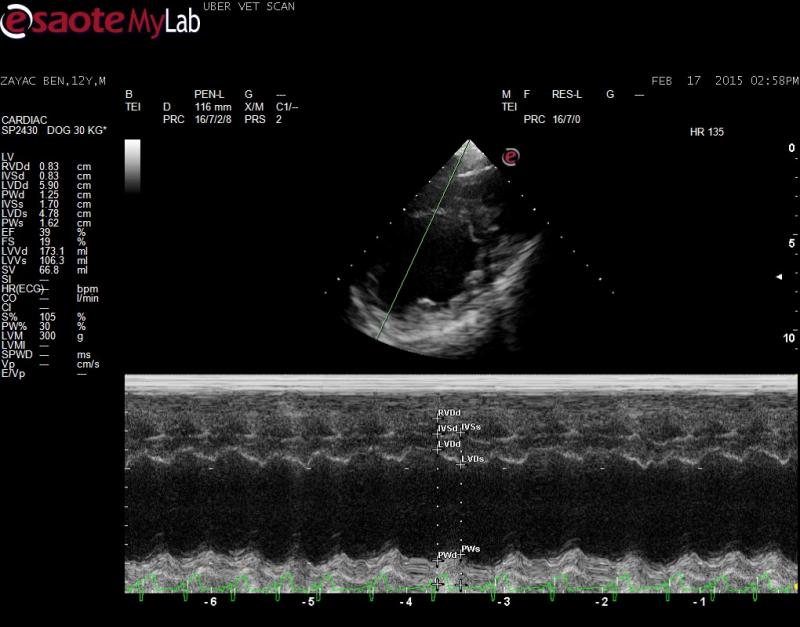

– echo did show a dilated LV and poor systolic function, decreased FS%, elevated EPSS so I am concerend about occult DCM

Of course the clip you want, I did not save! I have added two tranverse right parasternal views, if this may help? They are slightly obliqued ๐